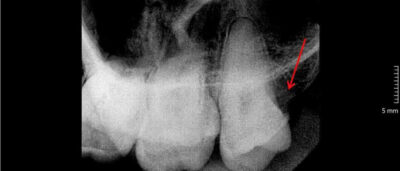

🔴 Răng khôn mọc lệch, mọc ngang

Đâm vào răng kế bê

Gây đau, kẹt thức ăn

- Dễ sâu răng số 7